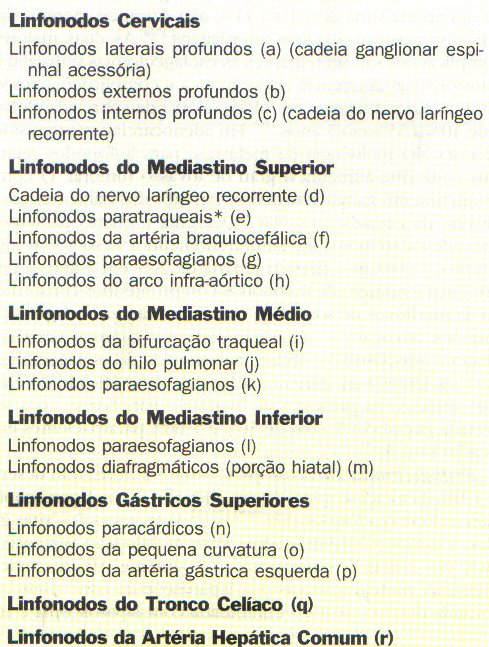

TORACOSCOPIA E ESTADIAMENTO MINIMAMENTE INVASIVO

O uso de VATS (cirurgia toracica video assistida) para estadiar o câncer esofágico tem-se mostrado altamente preciso, apesar de invasivo, para avaliação do estado linfonodal. A toracoscopia permite a visualização de toda a cavidade torácica e o esôfago, do desfiladeiro torácico ao hiato diafragmático, para biópsias de linfonodos, bem como para a visualização da extensão local da invasão.

Toracoscopia pode também visualizar doença metastática envolvendo as estruturas adjacentes, como traquéia, veia ázigos, aorta, pericárdio e diafragma.

A toracoscopia lateral direita é mais frequentemente realizada para que o esôfago possa ser visualizado e manipulado sem a interferência da aorta. A toracoscopia esquerda é usada quando o paciente tem suspeita de achados nos linfonodos à esquerda, a partir de estudos radiológicos prévios.

A laparoscopia é útil na avaliação e biopsia do tronco celíaco, da superfície peritoneal, da junção gastroesofágica e do fígado.

A laparoscopia complementa a toracoscopia para a promoção de um método de estadiamento preciso minimamente invasivo. A ultra-sonografía laparoscópica pode visualizar linfonodos tão pequenos quanto 3 mm de diâmetro com resolução comparável à da USE para potencialmente aprimorar a precisão do estadiamento global do TNM.

Esofagectomia Toracoscópica.

Muitos autores têm descrito o uso da toracoscopia vídeo-assistida (VATS) ou laparoscopia para realizar a esofagectomia.

As técnicas descritas incluem:

- uma laparotomia-padrão com mobilização toracoscópica do esôfago,

- uma técnica totalmente laparoscópica transiatal,

- mobilização gástrica laparoscópica com minitoracotomia direita

- técnica combinada com laparoscopia e toracoscopia com mobilização toracoscópica do esôfago seguida de mobilização gástrica laparoscópica

A esofagectomia toracoscópica tem três estágios:

- dissecção toracoscópica do esôfago torácico

- mobilização laparoscópica do conduto gástrico

- a anastomose cervical.

Estudos relatando a esofagectomia toracoscópica indicam mortalidade operatória entre 0% e 13,5%.

A morbidade tem sido relatada entre 27% e 55%.